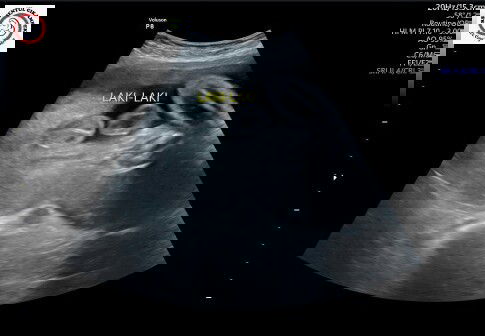

Usia kehamilan 29 minggu... Jk sudah terliahat apakah ini udah positif bunda bunda?

iya itu dedeknya cowok bun udah fiks 😊